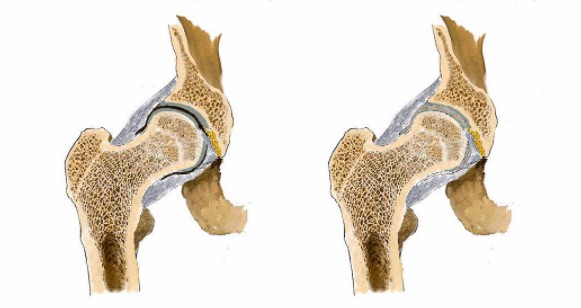

看男孩不說話,醫(yī)生繼續(xù)說道:“你的HLA-B27顯示陰性,如果是陽性就可以確診是強(qiáng)直性脊柱炎,現(xiàn)在只能排查……如果確診是強(qiáng)直性脊柱炎,就要就要及早治療,因?yàn)檫@個(gè)病是不可逆的,我們只能延緩它病程進(jìn)度……”